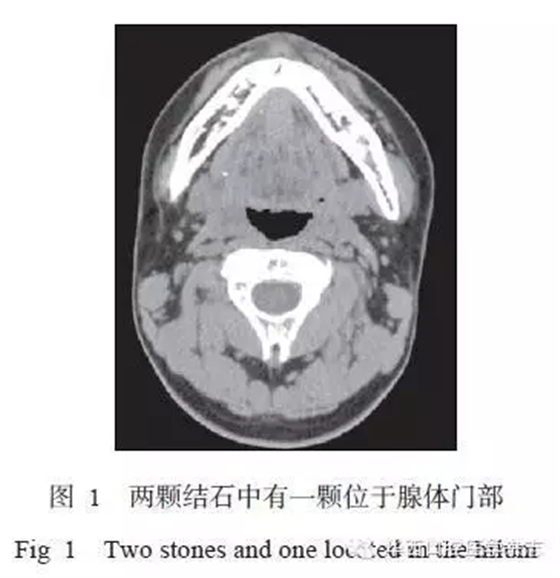

所有患者術(shù)前均行下頜骨CT[7]及唾液腺功能顯像檢查,結(jié)石位置要求位于下頜牙列雙側(cè)最后點(diǎn)連線后方,或位于下頜下腺腺體內(nèi)。若為多顆結(jié)石,至少有一顆符合此標(biāo)準(zhǔn)(圖1)。術(shù)前唾液腺功能檢查提示患側(cè)攝锝功能基本正常,排泌功能明顯下降。排除標(biāo)準(zhǔn):患側(cè)唾液腺無(wú)攝锝功能。